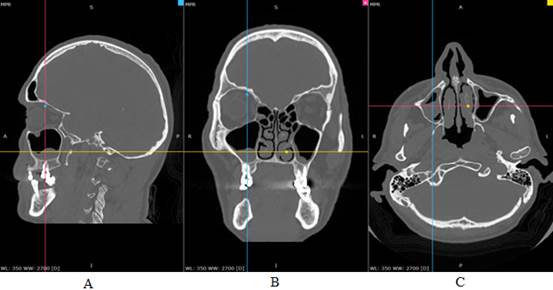

/Alikariyev.files/image003.jpg)

Рисунок 3. Женщина, 25 лет. МСКТ придаточных пазух. Патологические массы обеих гайморовых пазух мягкотканной плотности, неоднородной структуры на КТ: A- в сагиттальной проекции; B- во фронтальной проекции; С- в аксиальной проекции.